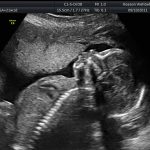

Second Trimester Ultrasound Scans: Everything You Need To Know

You have passed your first trimester milestone! Must read Here are Second Trimester Ultrasound Scans: Everything You Need To Know.